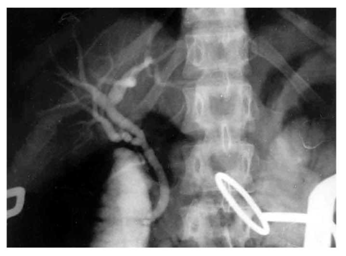

- דלף מרתי נובע מ:

- קשירה לקויה של צינור כיס המרה או התרת הקשר ממנו (תצלום 22.8). במצב זה נוצר נצור כבדי הדורש התערבות. זו יכולה להיות כירורגית - על-ידי כניסה מחדש לבטן וקשירת הצינור, או הכנסת תותב לכולדוכוס שחוסם את מוצא צינור כיס המרה, מקטין את הדלף ובליווי ניקוז מקומי ראוי ייסגר הדלף מעצמו;

- אי-זיהוי צינור אברנטי (Aberant duct) שלא נקשר. ברוב המקרים, דלף זה מפסיק מעצמו;

- חבלה לכולדוכוס שלא זוהתה. זו יכולה להיסגר מעצמה, אך עלולה לגרום היצרות מאוחרת של הכולדוכוס. אם הדלף אינו פוסק, הוא מחייב התערבות כירורגית. לעתים, אוסף מרתי כזה אינו מתנקז, מזדהם ויוצר מורסה תת-כבדית, הדורשת התערבות כירורגית לניקוזה.